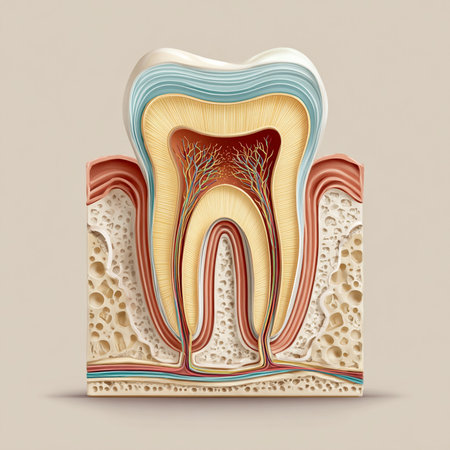

A close-up view of an anatomical model of a human molar tooth's cross-section. The white enamel cap transitions to yellow dentin, revealing the red pulp chamber and root canals within. The surrounding bone structure is depicted with porous texture in beige and red hues. The background is a solid, deep blue.

Detailed depiction of a tooths anatomy highlighting its internal structure and layers.

Tooth model displaying its complex internal structure including enamel, dentin, pulp, and root canals, standing against a vibrant background of colorful, out of focus lights

Dental tooth cross section model showing enamel, dentin, pulp, gum and root structures against a soft colorful bokeh background for oral health education and dentistry study

Anatomical intricacy: tooth structure, nerve, with a visible cartilaginous stage, detailed layers and components of a tooth, emphasizing the complex interplay of dental anatomy

This artwork intricately depicts the anatomy of a tooth along with its supporting tissues.

Human tooth cross section. 3d illustration

This image provides a detailed cross-section view of a human tooth, revealing the inner anatomy including the root pulp and surrounding bone structures. It is an educational and informative visual aid

Detailed cross-section of a human tooth displaying enamel, dentin, pulp, and root anatomy. Educational medical illustration on a gradient blue background.